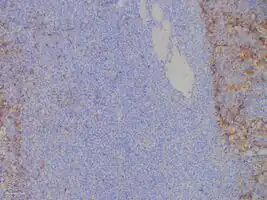

Bone marrow biopsies are performed to ensure the disease is localised; and in SPB or extramedullary plasmacytoma there will not be an increase of monoclonal plasma cells. Tissue biopsies of SPB and extramedullary plasmacytoma are used to assess the phenotype of the plasma cells. Histological analyses can be performed on these biopsies to see what cluster of differentiation (CD) markers are present and to assess monoclonality of the cells. CD markers can aid in the distinction of extramedullary plasmacytoma from lymphomas.[5][9]

Association with the Epstein–Barr virus

Rarely, the Epstein–Barr virus (EBV) is associated with multiple myeloma and plasmacytomas, particularly in individuals who have an immunodeficiency due to e.g. HIV/AIDS, organ transplantation, or a chronic inflammatory condition such as rheumatoid arthritis.[11] EBV-positive multiple myeloma and plasmacytoma are classified together by the World Health Organization (2016) as Epstein–Barr virus-associated lymphoproliferative diseases and termed Epstein–Barr virus-associated plasma cell myeloma. EBV-positivity is more common in plasmacytoma than multiple myeloma. The tissues involved in EBV+ plasmacytoma typically show foci of EBV+ cells with the appearance of rapidly proliferating immature or poorly differentiated plasma cells.[12] These cells express products of EBV genes such as EBER1 and EBER2. EBV-positive plasmacytoma(s) is more likely to progress to multiple myeloma than EBV-negative plasmacytoma(s) suggesting that the virus may play a role in the progression of plasmacytoma to multiple myeloma.[13]